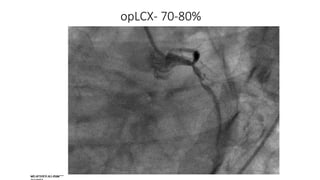

opLCX- 70-80%, dLCX- 40-50%

opLCX- 70-80%